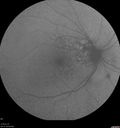

82 year old man with hemorrhagic PCV in temporal macula in the left eye.

Polypiodal Choroidal Vasculopathy - Temporal Macula - Left eye330 views82 year old man with asymptomatic PCV in the left eye. Vision 20/50 OD, 20/32 OS did well with Lucentis     (0 votes)